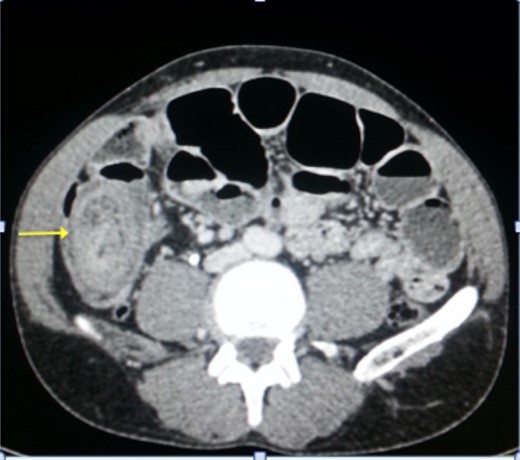

Upon laparotomy, we found an ileocecal intussusception, with mesenteric lymphadenopathies and a dilation of the whole small bowel (Fig. 3). We performed a right hemicolectomy, without attempting to reduce the intussusception, and an end-to-end ileotransverse anastomosis.